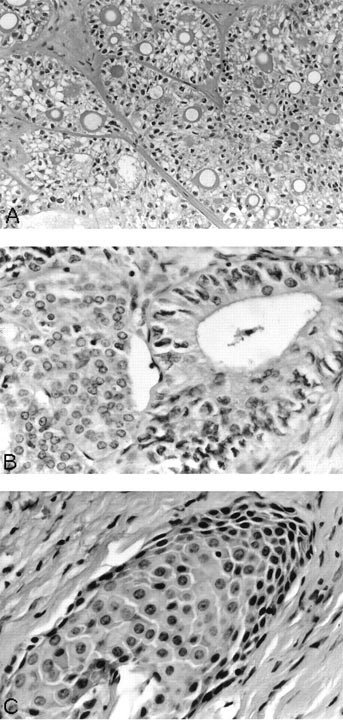

Microscopically, in all cases, the non-neoplastic thyroid parenchyma showed lymphocytic thyroiditis. The tumor cells were arranged in small islands, anastomosing cords, and narrow strands and displayed prominent squamous differentiation characterized by intercellular bridges and keratin pearl formation. Glandular structures resembling mucous cysts were noted in two cases (Fig. 4). The background stroma in the main tumor mass revealed marked sclerosis and a mixed inflammatory infiltrate with prominent eosinophilia (Fig. 4B). Lymphatic permeation was identified in one case with extensive lymph node involvement. Two cases revealed a separate focus of follicular variant of papillary thyroid carcinoma and papillary microcarcinoma. Both these lesions were present in the same lobe away from the main tumor mass.

Sclerosing mucoepidermoid carcinoma with eosinophilia (SMECE). A, tumor cells arranged in cords and nests in a background of sclerosis and lymphocytic thyroiditis. B, another view of SMECE showing tumor nests with mucous cyst formation in a background of sclerosis. C, high-power view showing tumor nest in a background eosinophil-rich (arrow) inflammatory infiltrate. D, squamous and glandular differentiation. E, a positive mucicarmine stain highlighting the mucin production in SMECE.